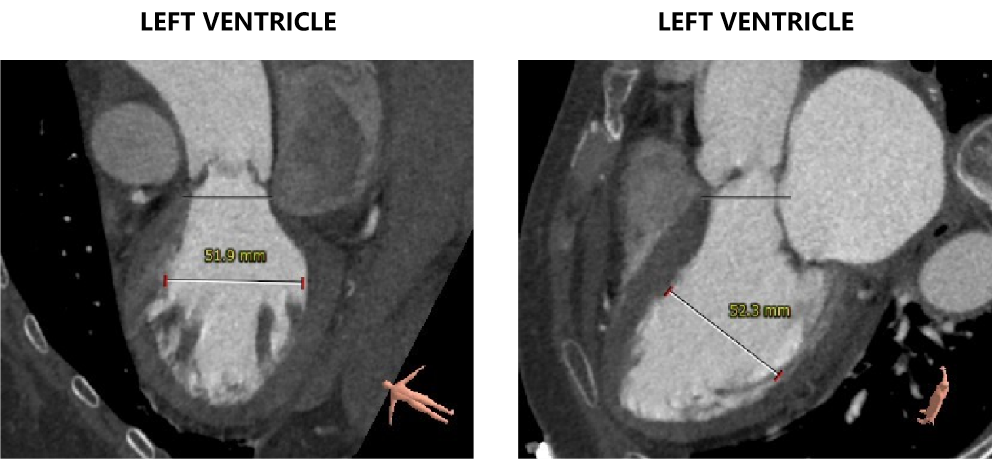

心室情况:

左室前后径28.7mm,左室最小径13.6mm,瓣环下6mm存在心肌膨出,

左心室影像:

左室腔增大,心室壁未见明显增厚。